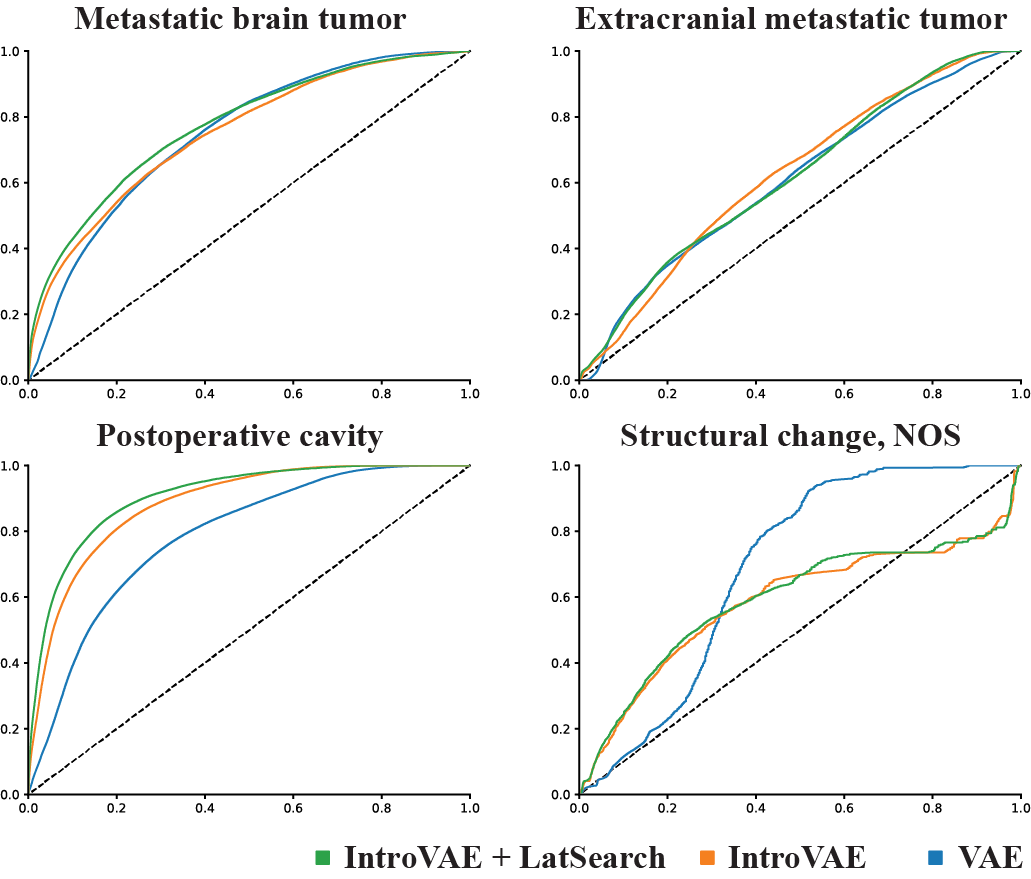

Fig. 6 shows the rectified ROC curves, which were calculated by considering the voxels inside the body only. The detection performance (mean standard deviation) based on the rectified ROC–AUCs is summarized in Table I. It can be seen that metastatic brain tumor and postoperative cavity were detected with a sufficient ROC–AUC exceeding 0.7. Between these two classes, IntroVAE+LatSearch outperformed the other two image reconstruction networks, namely VAE and IntroVAE, where the order of the higher detectability was compatible with the higher anatomical fidelity. Meanwhile, we discovered a low precision due to the much higher prevalence of “normal” voxels over “abnormal” voxels; this can yield a larger number of false-positive voxels.